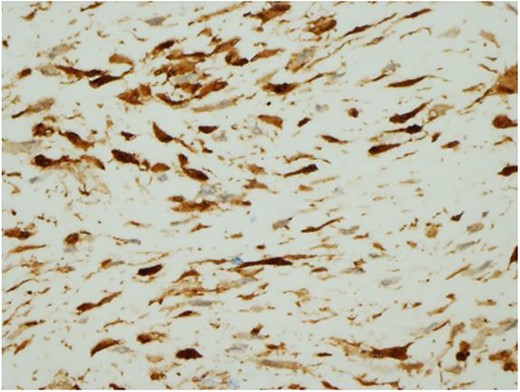

Ultrasound guided biopsy was performed, which showed spindle cells fascicles with collagen formation. The cells were stained positive to beta-catenin nuclear staining, and negative for SMA, CD34, Desmin and S100 (Figs 3 and 4). The diagnosis of desmoid fibromatosis was confirmed.

Histopathological findings. The tumour cells are positive for beta-catenin (H&E ×400).